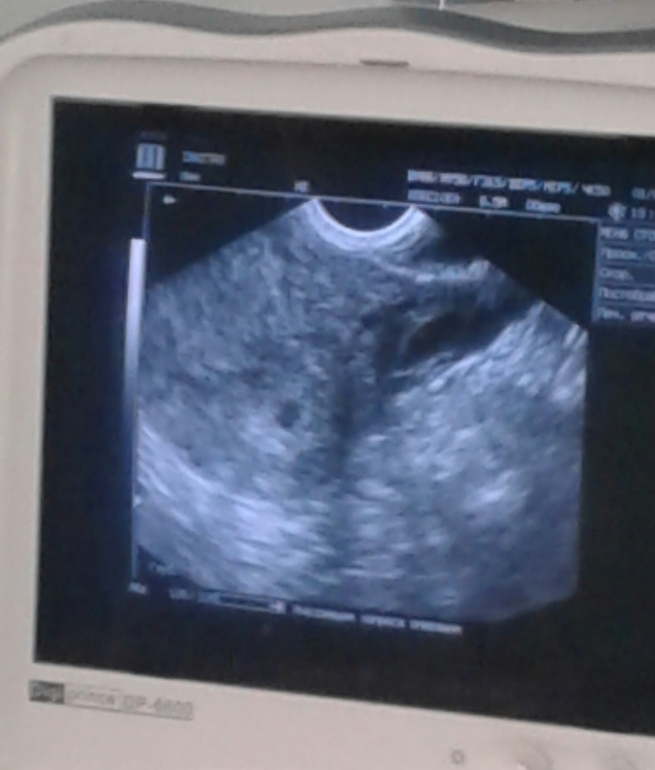

Нас нашли!!!мое крохотное темное пятнышко в самом дне матки! Уже целых 7 мм))) Соответствует сроку 5 нед 3 дня.

Жт справа 29*25. Эндометрий 14 благодаря Дивигелю)

И напоследок,всем привет от крохи! Наша первая фоточка